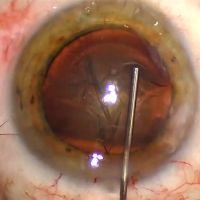

¿Dónde está el foco? - Enfoftalmitis mixta

Dr. Gonzalo FontánInfeccion MIXTA, tanto bacteriara como fúngica a nivel intraocular y corneal. Se realizo vitrectomia + transplante corneal penetrante descentrado. -